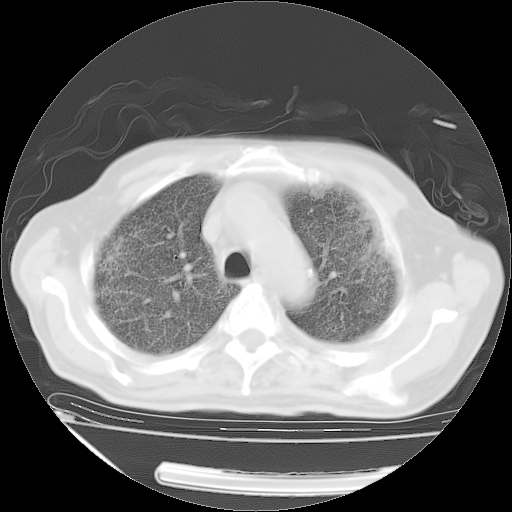

甲强龙80mg/日+抗结核治疗(异烟肼+利福霉素+乙胺丁醇)10天。复查肺部CT。

治疗10天肺部CT

仔细阅读病史资料和CT,我觉得两肺粟粒结核要高度怀疑。

今天带四次肺CT片到市医院,影像科4~5个主任都认为不考虑粟粒性肺结核。主要理由是在3月19日、4月2日、4月27日的CT片没有见到确切异常(肺结核)影像。影像科主任们建议找呼吸内科主任,呼吸内科主任认为首先考虑粟粒性肺结核。